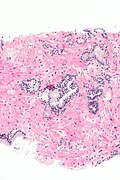

Atypical small acinar proliferation - top-left of image. H&E stain. | |

Microscopic

Features:

- Atypical appearing acini - see criteria for prostate adenocarcinoma.

- Limited extent - key feature.

- Less than six glands.†